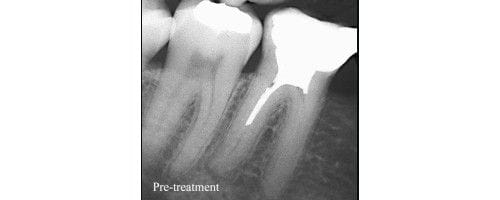

When a cavity reaches the pulp and when the patient experiences mild or excruciating pain, root canal is advised. Depending upon the severity of the pain from mild , moderate to severe, local anesthesia is injected. Local anesthesia could be infiltrated where the branches of the main nerve are blocked or it could be a block where the main nerve is anaesthetized.

Single rooted anterior teeth are not at all painful as compared to the multirooted molar teeth. The pain caused during root canal depends even on the pain threshold of an individual and that varies from patients to patients. Pain threshold is the capacity of bearing certain level of pain. In some individuals, root canal can be done without prior anesthesia. One of the easiest methods to access pain is to ask the patient to rate his pain on a scale of 1 to 10.

Sometimes, during the treatment, even the patients give their past dental history to their dentist when it comes to getting a root canal treatment done. Pain management strategies like use of analgesic medications, cold pack application are also used. Root canal therapy is a must tooth saving procedure which we advise to the patients to undergo in order to save their natural tooth as it is beneficial for functional and aesthetic purpose.